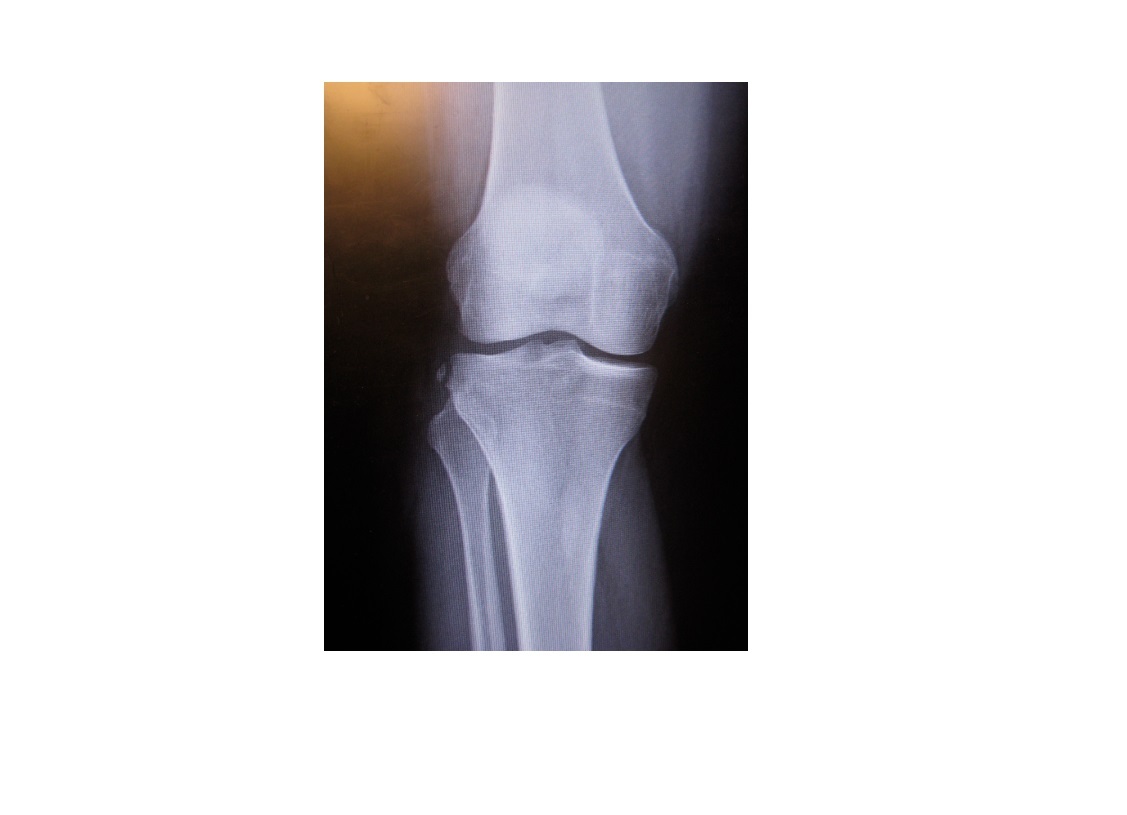

Segond fracture

Lateral tibial plateau

Associated with ACL tear (75%) and internal rotation